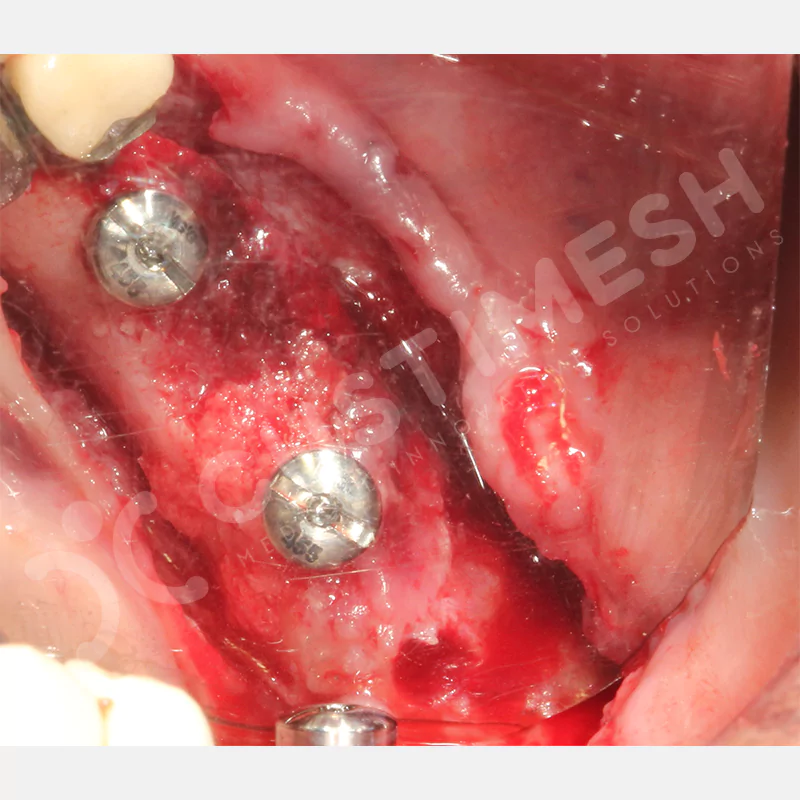

VAKA 1